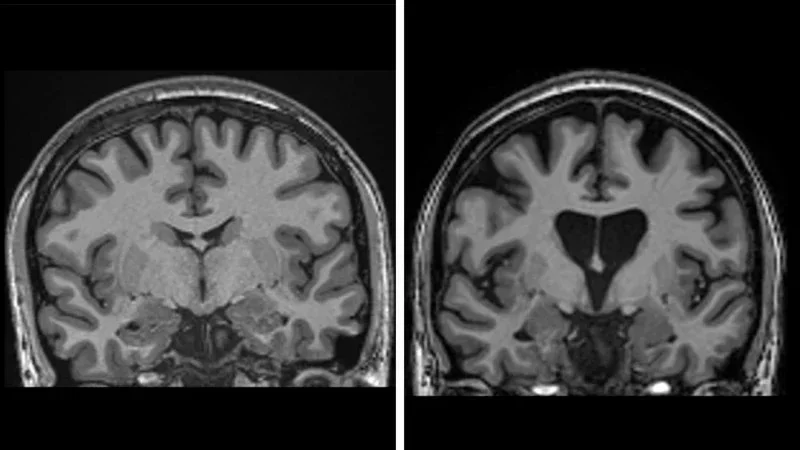

Олимлар Хантингтон касаллигининг ривожланишини 4 баробар секинлаштиришга муваффақ бўлишди